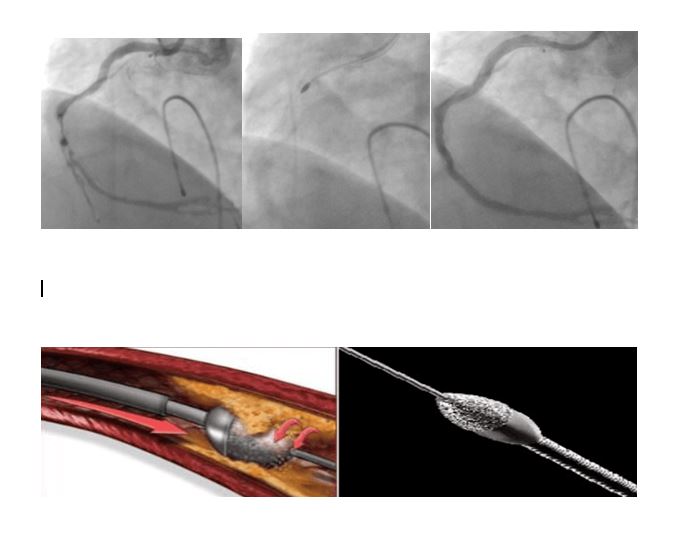

Karaman Eğitim ve Araştırma Hastanesinde İlklere İmza AtılıyorKaraman'da sağlıkta gelişim adına ilklere imza atan Karaman Eğitim ve Araştırma Hastanesinde ilk kez uygulanan ve Kardiyoloji Uzmanı olarak görev yapan Doç. Dr. Oğuz KILIÇ’ın yönetiminde nitelikli bir ameliyat daha başarı ile gerçekleştirildi.Konuyla ilgili olarak Karaman Eğitim ve Araştırma Hastanesinde Kardiyoloji Uzmanı olarak görev yapan Doç. Dr. Oğuz KILIÇ’ yaptığı açıklamasında şu ifadelere yer verdi:“Kalp damar hastalığı, koroner arter denilen, kalbi besleyen damarların tıkanması sebebiyle olmaktadır. Bu tıkanmaların en sık görülen sebebi ise ateroskleroz olarak adlandırılan damar duvarında yağlı plakların birikip zaman içerisinde damar boşluğuna doğru ilerleyip damar içinde kan akışını engellemesidir. Yağlı plaklar bazen kireçlenerek daha katı ve sert plaklar oluşturmaktadır. Bu kireçlenmiş plaklar ise bazen tıkanıklığı açmakta kullanılan balon/stent gibi malzemelerin geçişini engellemekte ve imkânsız kılmaktadır. Sonuçta balon/stent damar tıkanıklığı içerisinden geçemediği için tıkanıklık açılamamaktadır. Ek olarak, uygun olmayan malzemelerin kullanılması ile damarda yırtılma ve delinme gibi sorunlara yol açarak hastanın hayatını tehlikeye atan durumlar ortaya çıkmaktadır.Bu sert plakların açılmasında birtakım yeni teknolojiler kullanıma girmiştir. Bunlardan biri rotablatör (tıraşlama cihazı)’dür. Tıraşlama yöntemi ile damarı tıkayan kireçli plak yapısı parçalanarak darlıklar açılmakta, arkasından da balon/stent işlemi yapılmaktadır. Bu teknolojinin bir diğer faydası ise sert plaklara uygulanan stentin ileride tıkanma ihtimalini azaltmasıdır. Hastamızın sırasıyla; işlem öncesi, işlem esnasında ve işlem sonrasına ait sağ kalp damarına ait görüntüler izlenmektedir. Biz de merkezimizde ilk defa uyguladığımız bu işlemi başarı ile gerçekleştirdik ve hastamızı sağlığına kavuşturduk.”“Karaman Eğitim ve Araştırma Hastanesi Başhekimi Şükrü Salih TOPRAK ise yapmış olduğu açıklamada, “Başarılı bir şekilde gerçekleştirilen bu operasyonda görev alan uzmanları ve ekibini tebrik ediyor, hastalarımıza acil şifalar diliyorum. Hastaların yoğun bakımında takip sürecinin başarıyla sürmekte olup bu yöntemle uygun olan vakaların ameliyatlarının hastanemizde gerçekleştirilmesine devam edilecektir. Bundan sonra bu ameliyatların Karaman ilinde başarılı bir şekilde gerçekleşmesinden dolayı, hastaların il dışına gitmelerine gerek kalmayacaktır” şeklinde konuştu.